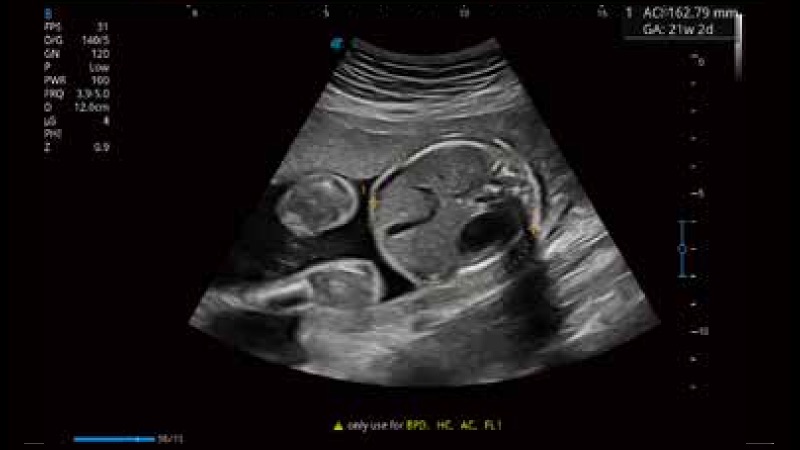

容积探头

凭借公海贵宾会员检测中心医疗先进的成像技术和优异的探头技术提供的清晰的图像表现,您可以更自信地做出临床决策。